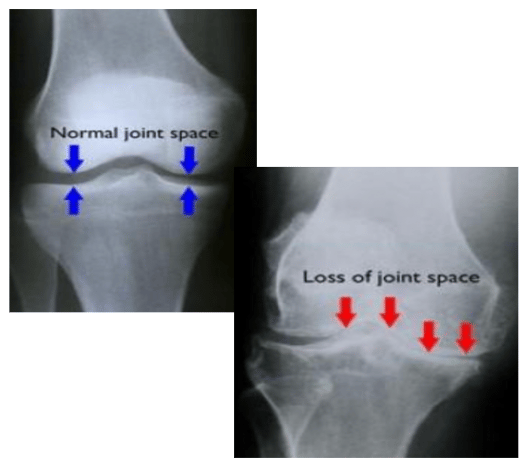

4. Worsening Radiographic Changes:

As your patient’s knee arthritis worsens symptomatically so do their radiographic findings. As time progresses, your initial and subsequent surveillance knee x-rays unequivocally confirm the initial subtle bony changes of joint-space narrowing have become bone-on-bone. Plus, now you would see the bony spurs (osteophytes) formation increase in numbers along with sclerosing lines. Also, the loss of smooth cortical bony surfaces or even the development of bony cysts would become more notable compared to when initially seen in some cases depending on the stage you assumed care of the patient during their arthritic journey.